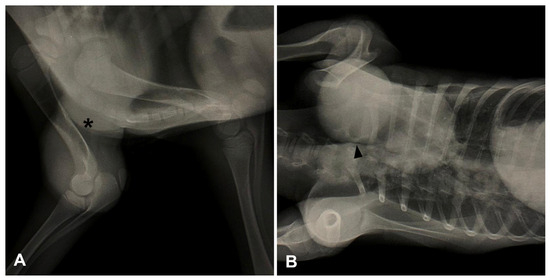

2. Case Series Presentation